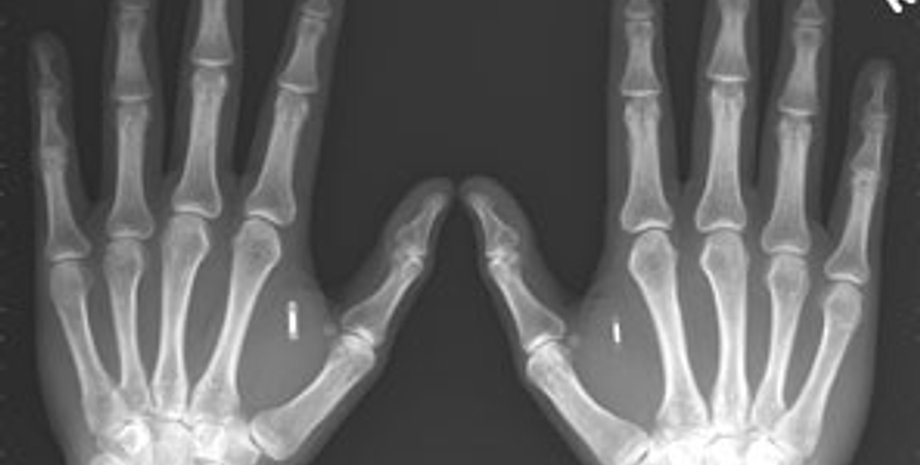

Перед тем, как изготавливать искусственную кость медикам будет нужно сделать рентгеновский снимок и томограмму поврежденного участка, чтобы в дальнейшем система изготовления костной ткани могла в точности воспроизвести размеры и форму поврежденной кости. Сообщается, что технология производства способна производить кости довольно замысловатой формы, например, челюсти или фрагменты черепа. Минимальная толщина искусственной кости составляет 1 мм, что более чем достаточно для подавляющего большинства костей в организме.